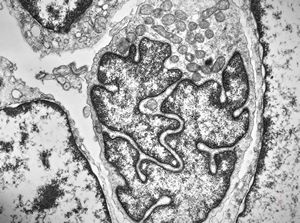

M, 11y. | mycosis fungoides v.s. - cerebriform nucleus of Sézary cell